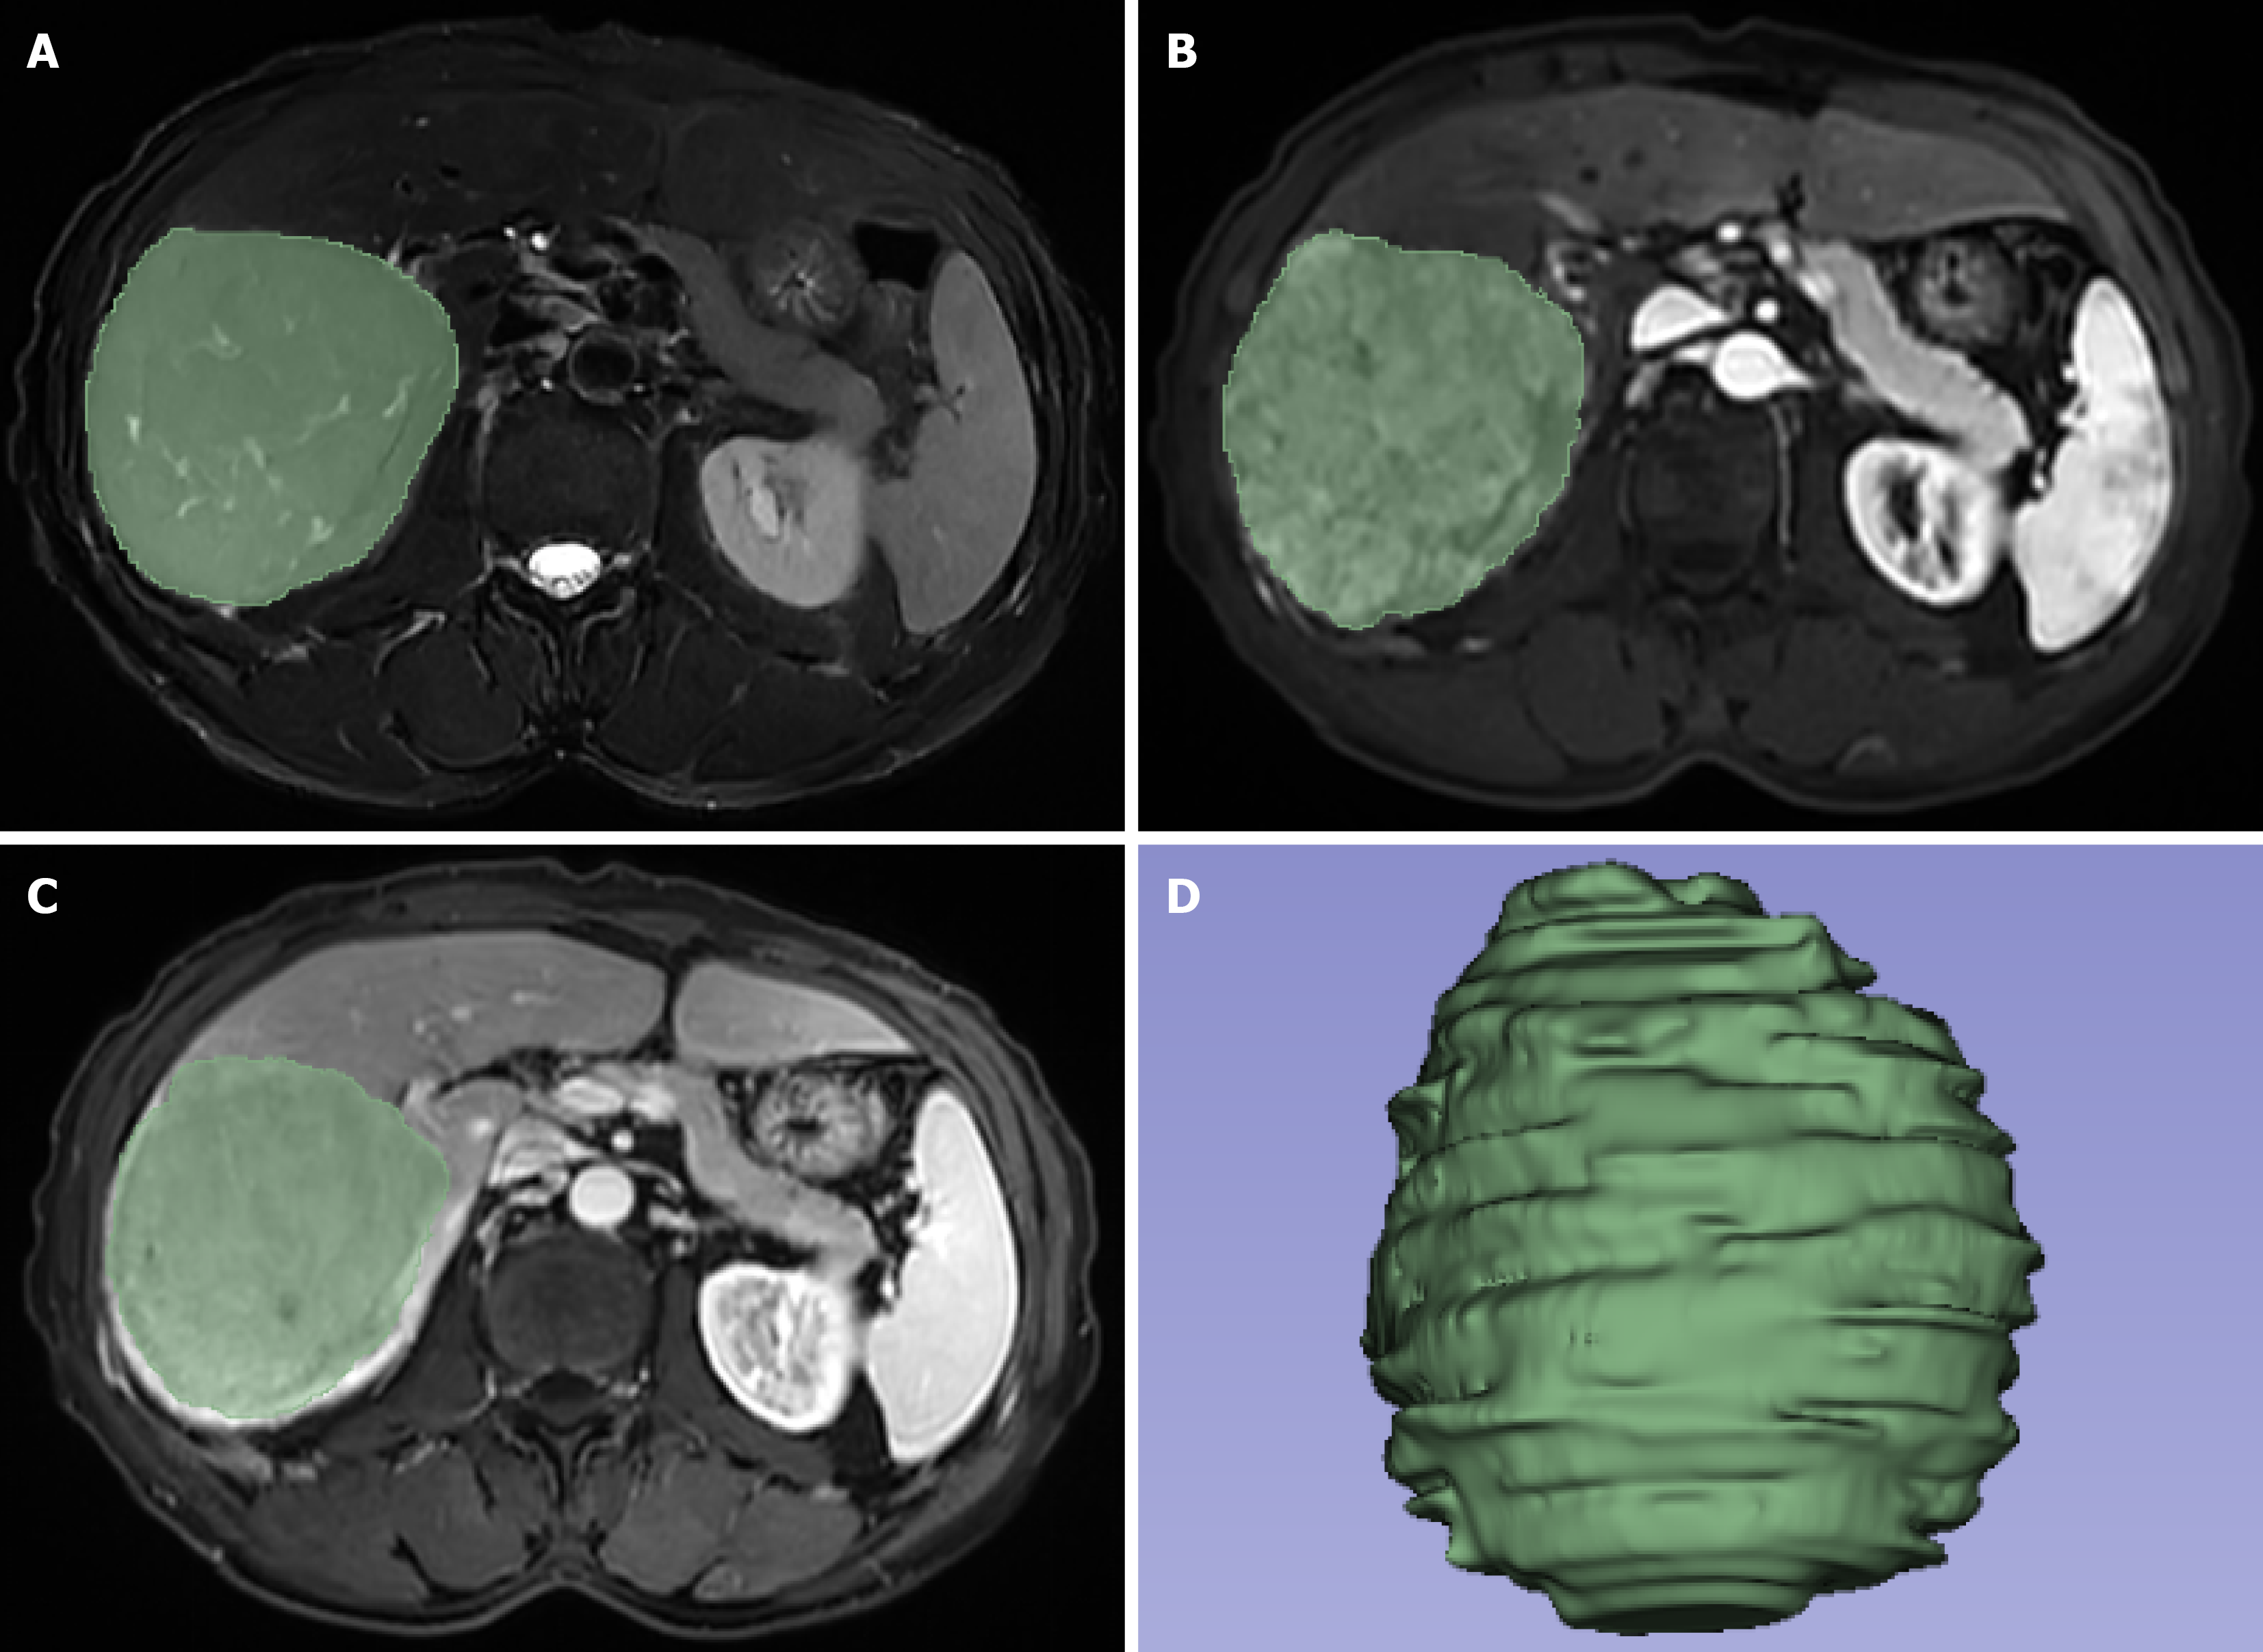

Figure 1 Region of interests along the edge of the lesion.

A: Fat-saturation T2-weighted imaging; B: Arterial phase image; C: Portal venous phase image; D: Three-dimensional image of the lesion.